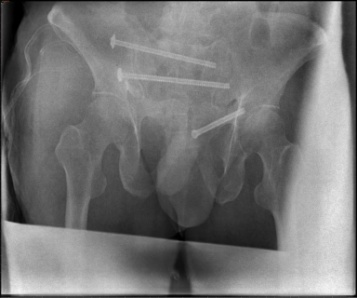

术前影像

术中,岳晓东主任依托HoloSight平台规划的置钉路线,精准的为患者进行骶髂关节螺钉固定。